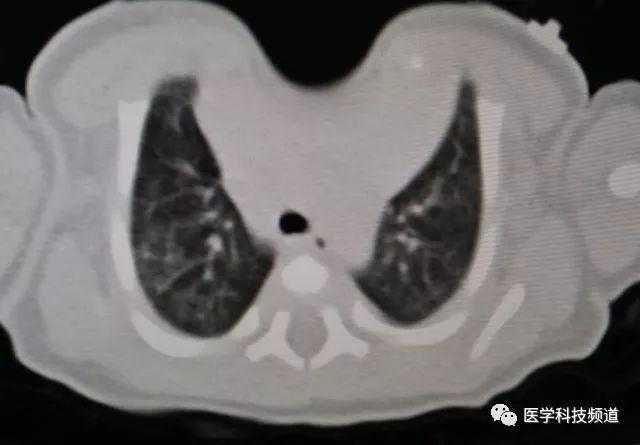

The patient was a one-month-old infant who was discovered to have an abnormality in the anterior chest wall shortly after birth. Specifically, there was a pronounced depression in the midline of the upper chest wall where the protection of bone structures was noticeably absent. The infant was diagnosed with sternal cleft and congenital heart disease. Due to the infant's poor health, surgical intervention has been postponed temporarily. Over time, the infant's condition gradually worsened, resulting in breathing difficulties and triggering a lung infection.

There is a noticeable depression in the center of the chest wall, accompanied by obvious paradoxical respiration. This area shows large-scale deficiency or absence of bone structures, with only about 1 cm of bone structure remaining at the inferior end of the sternum, connecting both sides of the chest wall. Additionally, the patient suffers from congenital heart diseases, including ventricular septal defect and patent foramen ovale, which have led to abnormal heart rhythms and sinus tachycardia.